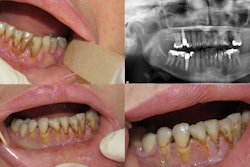

Intraoral images of the 70-year-old woman. Clinicians replaced the bridge on her upper right molars with individual temporary crowns. All images courtesy of Watanabe et al. Licensed under CC BY 4.0.In two other cases, collaboration between dentists and psychiatrists resulted in the patients requesting and receiving fewer treatments that would have exacerbated their symptoms, Watanabe and colleagues noted.

Intraoral images of the 38-year-old woman during her first visit (A) and revisit (B). Dental composite resin was constructed on her molars according to her demands. An anterior open bite can also be seen.Finally, a 48-year-old woman demanded occlusal adjustment for her improperly aligned teeth. After receiving orthodontic treatment, her symptoms worsened.

Intraoral images of the 48-year-old woman. All of the patient's teeth were in contact, but clinicians constructed dental composite resins on almost every lower tooth surface for occlusal adjustment after orthodontic treatment.Final thoughts